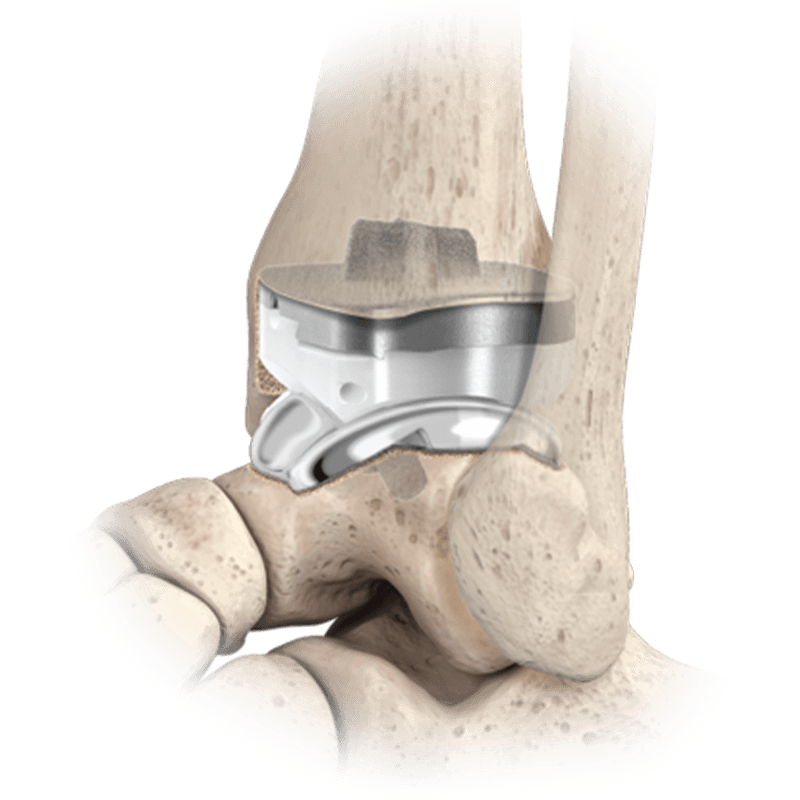

Arthroplasty

QUANTUM ® Total Ankle System

Addressing the complexity of TAR while allowing for reproducible outcomes